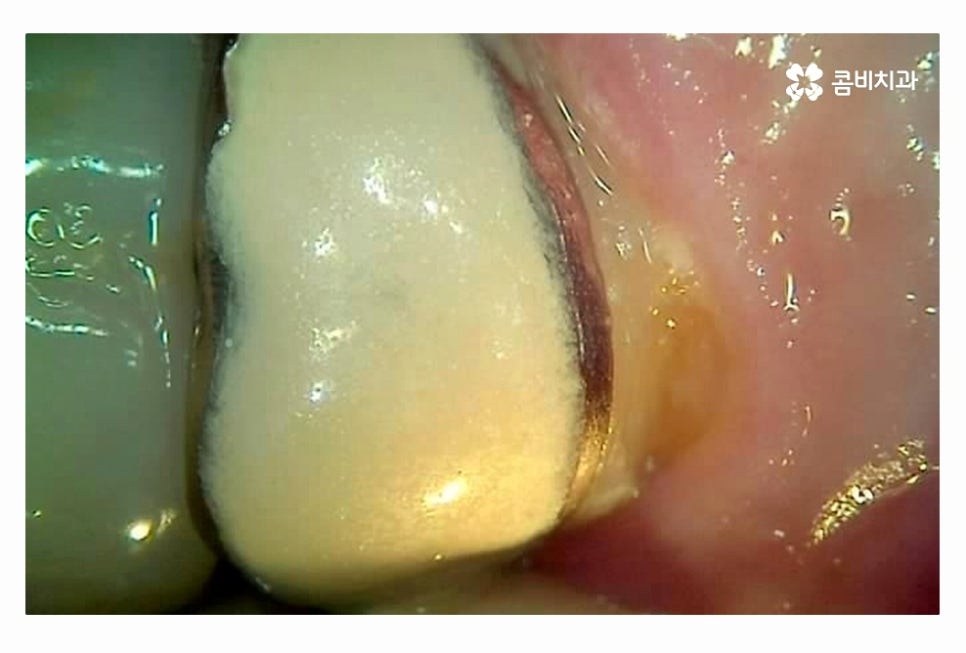

충치는 누구나 발생할 수 있고 과거에 레진이나 인레이 등의 치료를

했던 분들이라면 시간이 지날수록 주변 치아 혹은 치료에 쓰인 재료가

손상, 마모 등을 거치게 되는데 치아 속에 2차 충치가 발생하는 경우에는

그로 인한 치아 손상이 심각한 상황으로 커지는 경우가 많다고 할 수 있어요.

그렇기 때문에 이미 충치치료를 했던 부위라고 해서 안심해서는 안 되며

주기적으로 치과 검진을 실천해야 하겠고